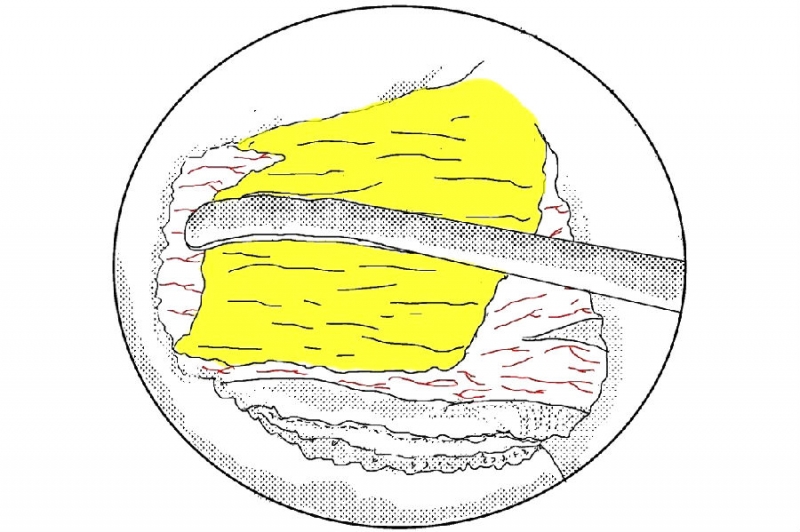

6. 使用骨凿将磨薄的下关节内缘凿除显露Corner和上关节突内缘;

7. 使用反向的椎板咬骨钳减压同侧Corner部位;

8. 减压的外界参考椎弓根内壁;

9. 切除椎弓根内缘同时松解黄韧带外缘;

10. 剥离黄韧带;